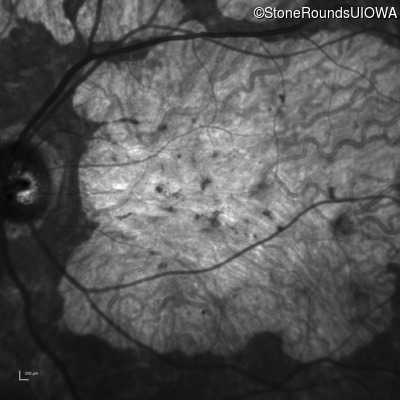

| Age at visit: 57 years |

| AR Stargardt Disease | ABCA4 | Cys205Phe TGC>TTC | Gly863Ala (G)GA>(G)CA | AR |